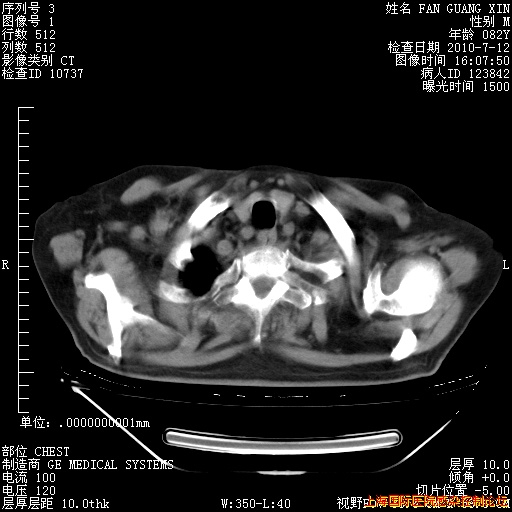

补发6月12日肺部CT肺窗

6月12日肺窗

6月12日纵膈窗